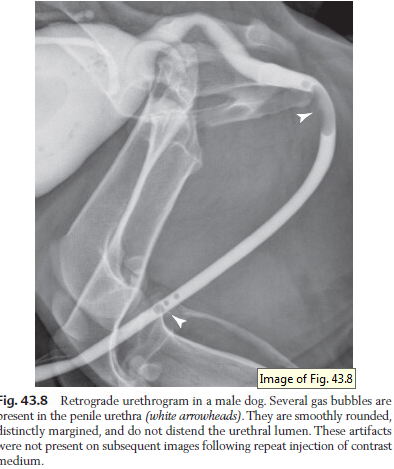

How can you tell the difference between a stone and air bubble on urethrogram?

Bubbles are smooth and stones are rough edges